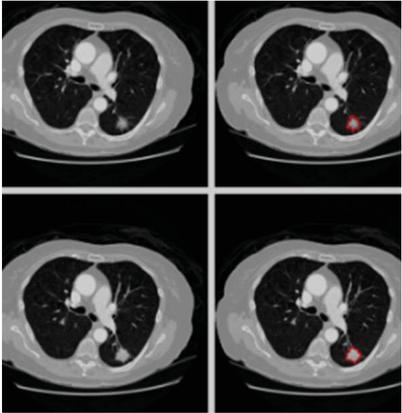

U-Net is used for lung nodule segmentation after data augmentation, offering accurate localisation and delineation of nodule boundaries – critical for precise diagnosis and therapy planning. The segmentation performance of U-Net is enhanced by its symmetric architecture with skip connections, which preserves fine features and facilitates the efficient learning of spatial hierarchies. U-Networks particularly well for lung nodule segmentation because it can handle sparse training data through augmentation and is resilient to changes in nodule size, shape, and location [20].

U-Net functions as a convolutional autoencoder, meaning that the input data is compressed by the network’s encoder and then reconstructed from this latent space representation by the decoder. The U-Net design consists of two paths: an expanding path (decoder) that employs transposed convolutions for accurate localisation, and a contraction path (encoder) that gathers the context of the input image, mostly made up of convolutional and pooling layers. In contrast to conventional autoencoders, U-Net uses stacks of max-pooling and convolutional layers in place of fully linked feed-forward layers. The Dense-UNet had a DSC of 0.93, which was excellent in the detail retention but had a higher memory requirement. In contrast, the U-Net outperformed both of them with a DSC of 0.94, providing the best balance among accuracy and computational efficiency, and it is presumably to be the most suitable for use in clinical applications [30, 31].

images

Figure 3 Segmented images for LIDC-IDRI.

Three convolutional blocks make up the expanding and contracting pathways. Every block in the contracting path consists of a 2 × 2 max-pooling layer after two convolutional layers. Each block in the expanding path consists of two convolutional layers, a dropout layer, a 2 × 2 up-sampling layer, and a concatenation with the matching block from the contracting path [22]. Two convolutional layers make up the linking path, and a 1 × 1 convolutional layer with sigmoid activation is the final output layer. U-Net’s skip connections maintain spatial information, combining high-level context (shapes, relationships within the image) with low-level spatial data (textures, edges) to produce high-quality segmentation. Segmented images from the LIDC-IDRI dataset are displayed in Figure 3. The RCBAM-CNN is then given the segmented output in order to classify lung nodules.